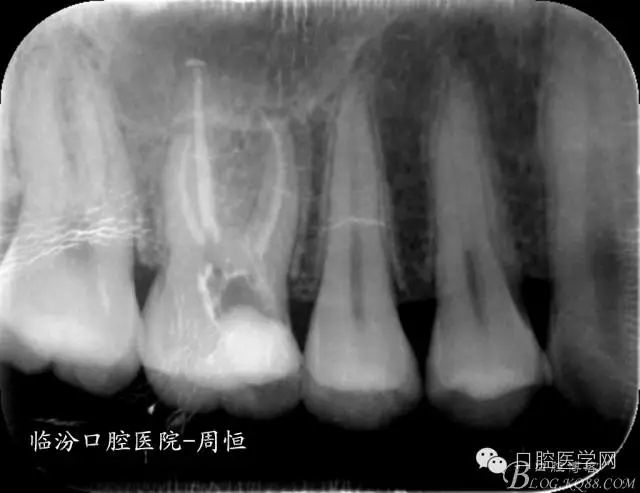

圖2 X示 根充后